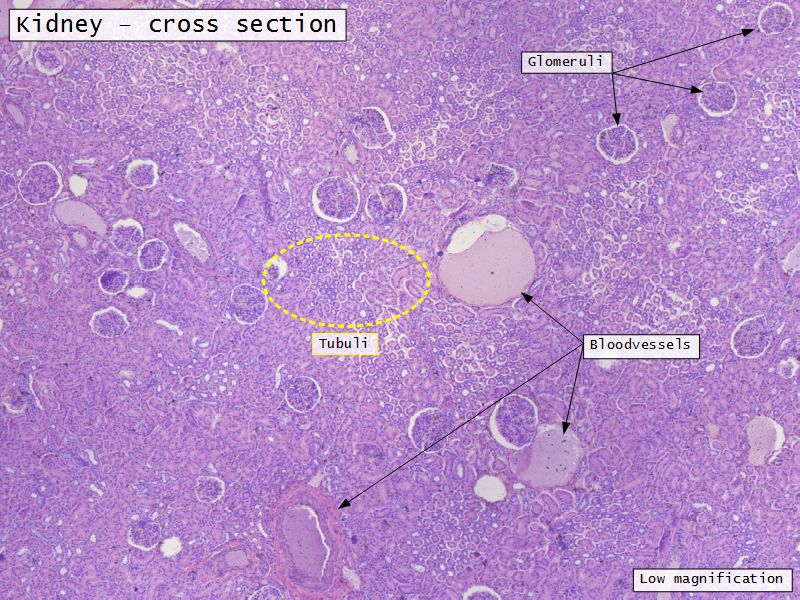

Appearance

- Cortex

- Renal corpuscles

- Convoluted tubules

- Medulla

- Loops of Henle

- Collecting tubules

Kidney lobule

- Group of neprons

- Open into branches

- Same collecting duct

- Not clearly demarcated

- Interlobular arteries/veins